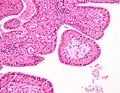

The appearance of this tumor under the microscope is unique. There are cystic spaces surrounded by two uniform rows of oncocytes, which are epithelial cells with abundant, granular, eosinophilic cytoplasm.[7] The cystic spaces have epithelium referred to as papillary infoldings that protrude into them. Additionally, the epithelium has lymphoid stroma with germinal center formation.